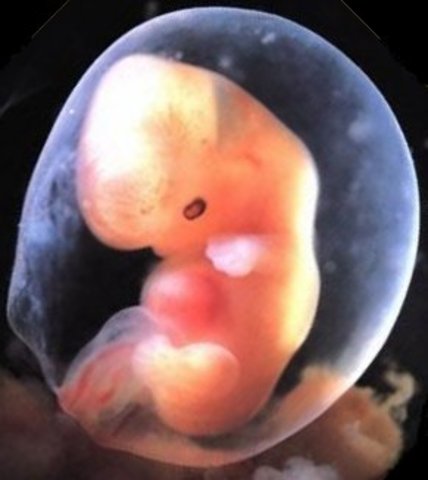

week 5

Amniotic fluid is building up. The embryo starts to grow.

• week 6

week 6

Embryo is about 8 mm in length. Spinal cord begining to close.

• week 7

week 7

One chamber of the heart is beating.arms and legs beging to form.